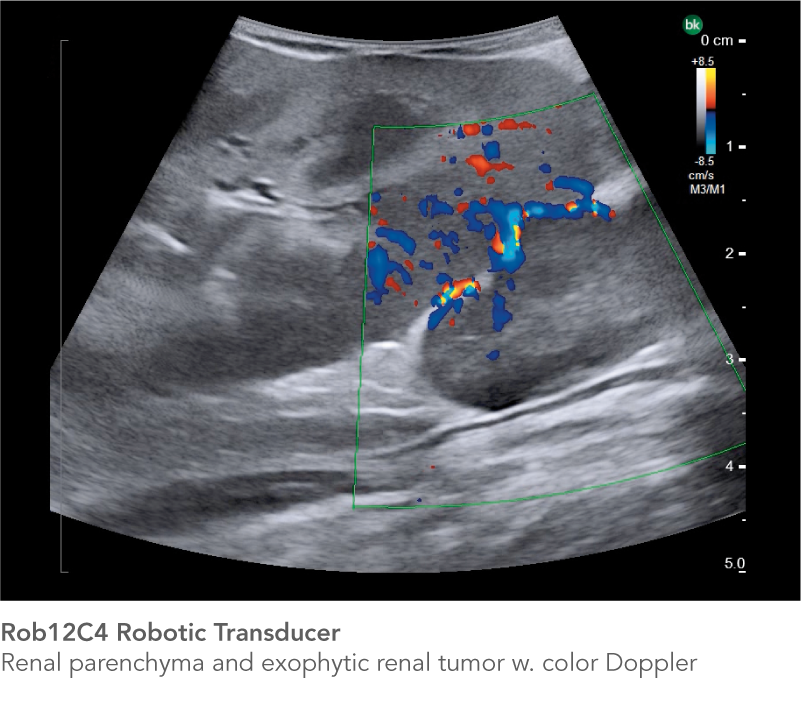

The Rob12C4 Robotic Transducer does more than Partial Nephrectomy. The high-resolution ultrasound transducer is designed to support robotics programs in a variety of procedures.

Partial Nephrectomy

See the information you need to achieve successful outcomes

Real-time intraoperative ultrasound helps you confirm tumor borders and depth, and minimize warm ischemia time, positive margins, damage to arteries, and resection of healthy tissue. The Rob12C4 transducer features a highly flexible cable and a small transducer profile, while the bk5000 offer's outstanding image quality with excellent anatomical details, enabling you to reach difficult-to-access anatomy and see the information you need to achieve successful outcomes.